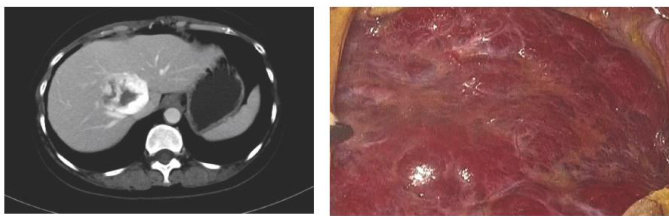

当体检单上蹦出个“肝血管瘤”,不少人心里会“咯噔”一下。但别慌,这东西绝大多数情况下就是个无害的“小血泡”,跟你担心的癌症完全是两码事。今天,咱们就来聊聊发现肝血管瘤后到底该怎么办。

一、肝血管瘤是个啥:带血的“海绵”

肝血管瘤和你想象中那类会疯长、会转移的“坏瘤子”(恶性肿瘤)不一样,它是肝脏里最常见的良性占位。(剩余1672字)